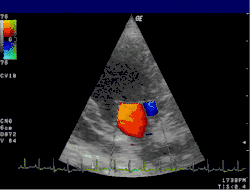

![]() | ![]() |

Severe MR | Legend |

1 Left atrium (LA) – 2 MR Jet, LV Left ventricle – RV Right ventricle – RA Right atrium |

An echocardiogram is commonly used to confirm the diagnosis of MR.[16] Color doppler flow on the transthoracic echocardiogram (TTE) will reveal a jet of blood flowing from the left ventricle into the left atrium during ventricular systole. Also, it may detect a dilated left atrium and ventricle and decreased left ventricular function.[6] A transesophageal echocardiogram can give clearer images if needed as the back of the heart can also be viewed.[17]